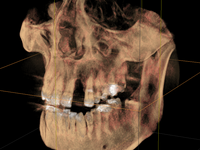

Bei nicht oder nicht vollständig durchgebrochenen Weisheitszähnen wird die darüber liegende Schleimhaut beiseite geschoben und der darüber liegende Knochen entfernt. Dann wird der Zahn mit einem Hebel entfernt. Ist dies aus anatomischen Gründen nicht im Ganzen möglich, wird das Durchtrennen des Zahnes notwendig. Das Trennen des Zahns ist obligat wenn die Platzverhältnisse keine andere Entfernungsmethode zulassen oder sich die Zahnwurzeln in unmittelbarer Nervnähe befinden. Die Wunde kann vernäht oder offen gelassen werden. Um Folgeschäden wie eine Taubheit der Unterlippe zu vermeiden kann präoperativ ein 3D DVT ( DIGITALES VOLUMENTOMOGRAMM ) zur Abklärung der Lagebeziehung von Wurzeln und Nerv sowie zur OP-Planung angefertigt werden.

Zu einer Wurzelspitzen-Entfernung wird Ihr Zahnarzt oder Kieferchirurg dann raten, wenn ein chronisch entzündlicher Prozess durch eine Wurzelbehandlung nicht behoben werden kann oder eine konventionelle Wurzelbehandlung nicht möglich ist. Auch wenn sich im Röntgenbild Veränderungen im Bereich der Wurzelspitze zeigen, die nicht eindeutig zuzuordnen sind, kann eine Wurzelspitzen-Resektion empfehlenswert sein. Um die Region der Wurzelspitzen genauer abzubilden ist es präoperativ möglich, durch ein 3D DVT (DIGITALES VOLUMENTOMOGRAMM) die Region dreidimensional abzubilden, um so eine bessere OP-Planung zu erhalten oder sich über die Frage der Erhaltungswürdigkeit des Zahns klar zu werden.

Solch ein Vorgehen erfordert allerdings auch eine möglichst exakte Diagnostik, die bei uns in der Regel dreidimensional mittels DVT erfolgt. So kann die Implantation vorher am Rechner dreidimensional simuliert werden, bevor sie am Patienten durchgeführt wird.

Kieferknochenspreizung / Dehnschrauben